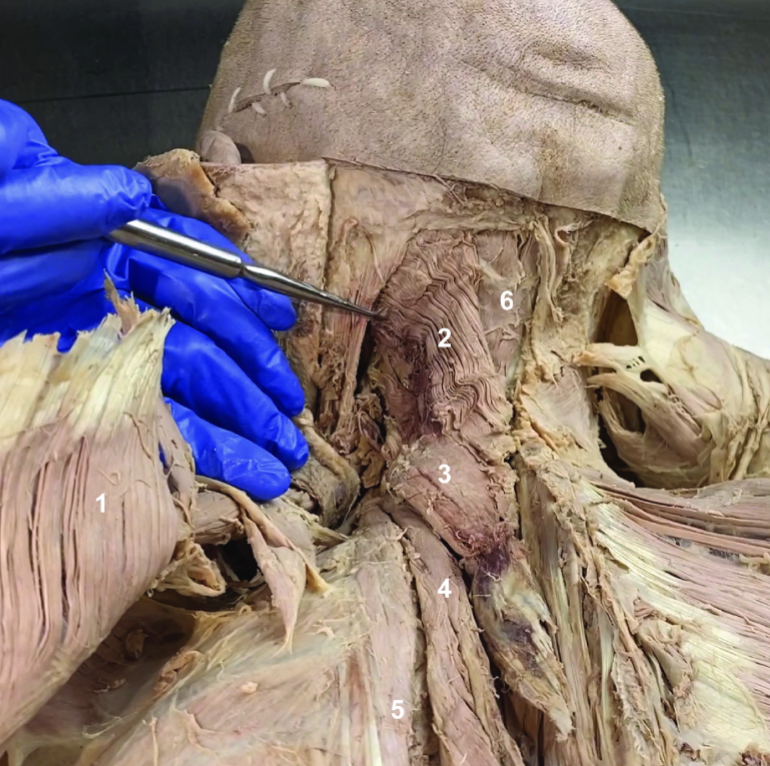

Trapezius (reflected)

ID structure

Spinal accessory n. (CN XI)

ID structure

Transverse cervical a.

ID structure

Levator scapulae

ID structure

Rhomboid minor

ID structure

Rhomboid major

ID structure

Rhomboids (reflected)

ID structure

Splenius capitis

ID structure

Splenius cervicis

ID structure

Longissimus

ID structure

Iliocostalis

ID structure

Semispinalis capitis